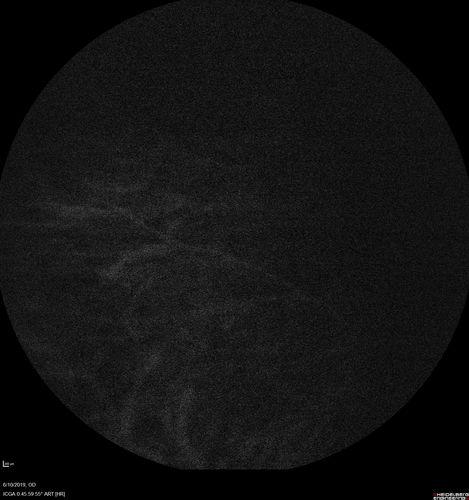

88 year old female with 2.5 mm elevated choroidal melanoma and melanosis oculi.  She also has geographic atrophy from AMD.  The right eye is the better eye with 20/40 vision.  After observation with growth, brachytherapy was done.